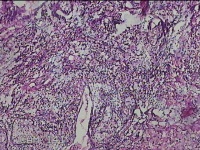

左侧腋下结节

性别

女

年龄

46岁

临床诊断

皮下结节

一般病史

发现左侧腋下一结节1周,伴局部隐痛不适,无发热。

标本名称

大体所见

灰白暗红色组织1.8x1.3x0.3cm一块,表面带梭形皮肤1.8x0.5cm,皮下见结节1.2x0.8cm,切开结节呈实性,切面灰白淡黄色,质软。

炎症性病变。